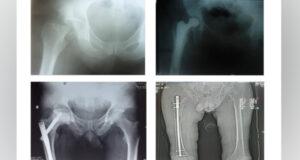

В Джальской больнице провели операцию по пересадке почек

В Национальном центре охраны материнства и детства проведена операция по пересадке почки. Общее количество трансплантаций достигло 76, из них 35 за счет госбюджета, сообщили в центре.  33-летний пациент О. Р. почти 2 года был на гемодиализе. Донором стал его родной брат — 44-летний Т. Н. После операции состояние пациентов оценивается как стабильное. Операция по пересадке проводится в центре с 2018 ...